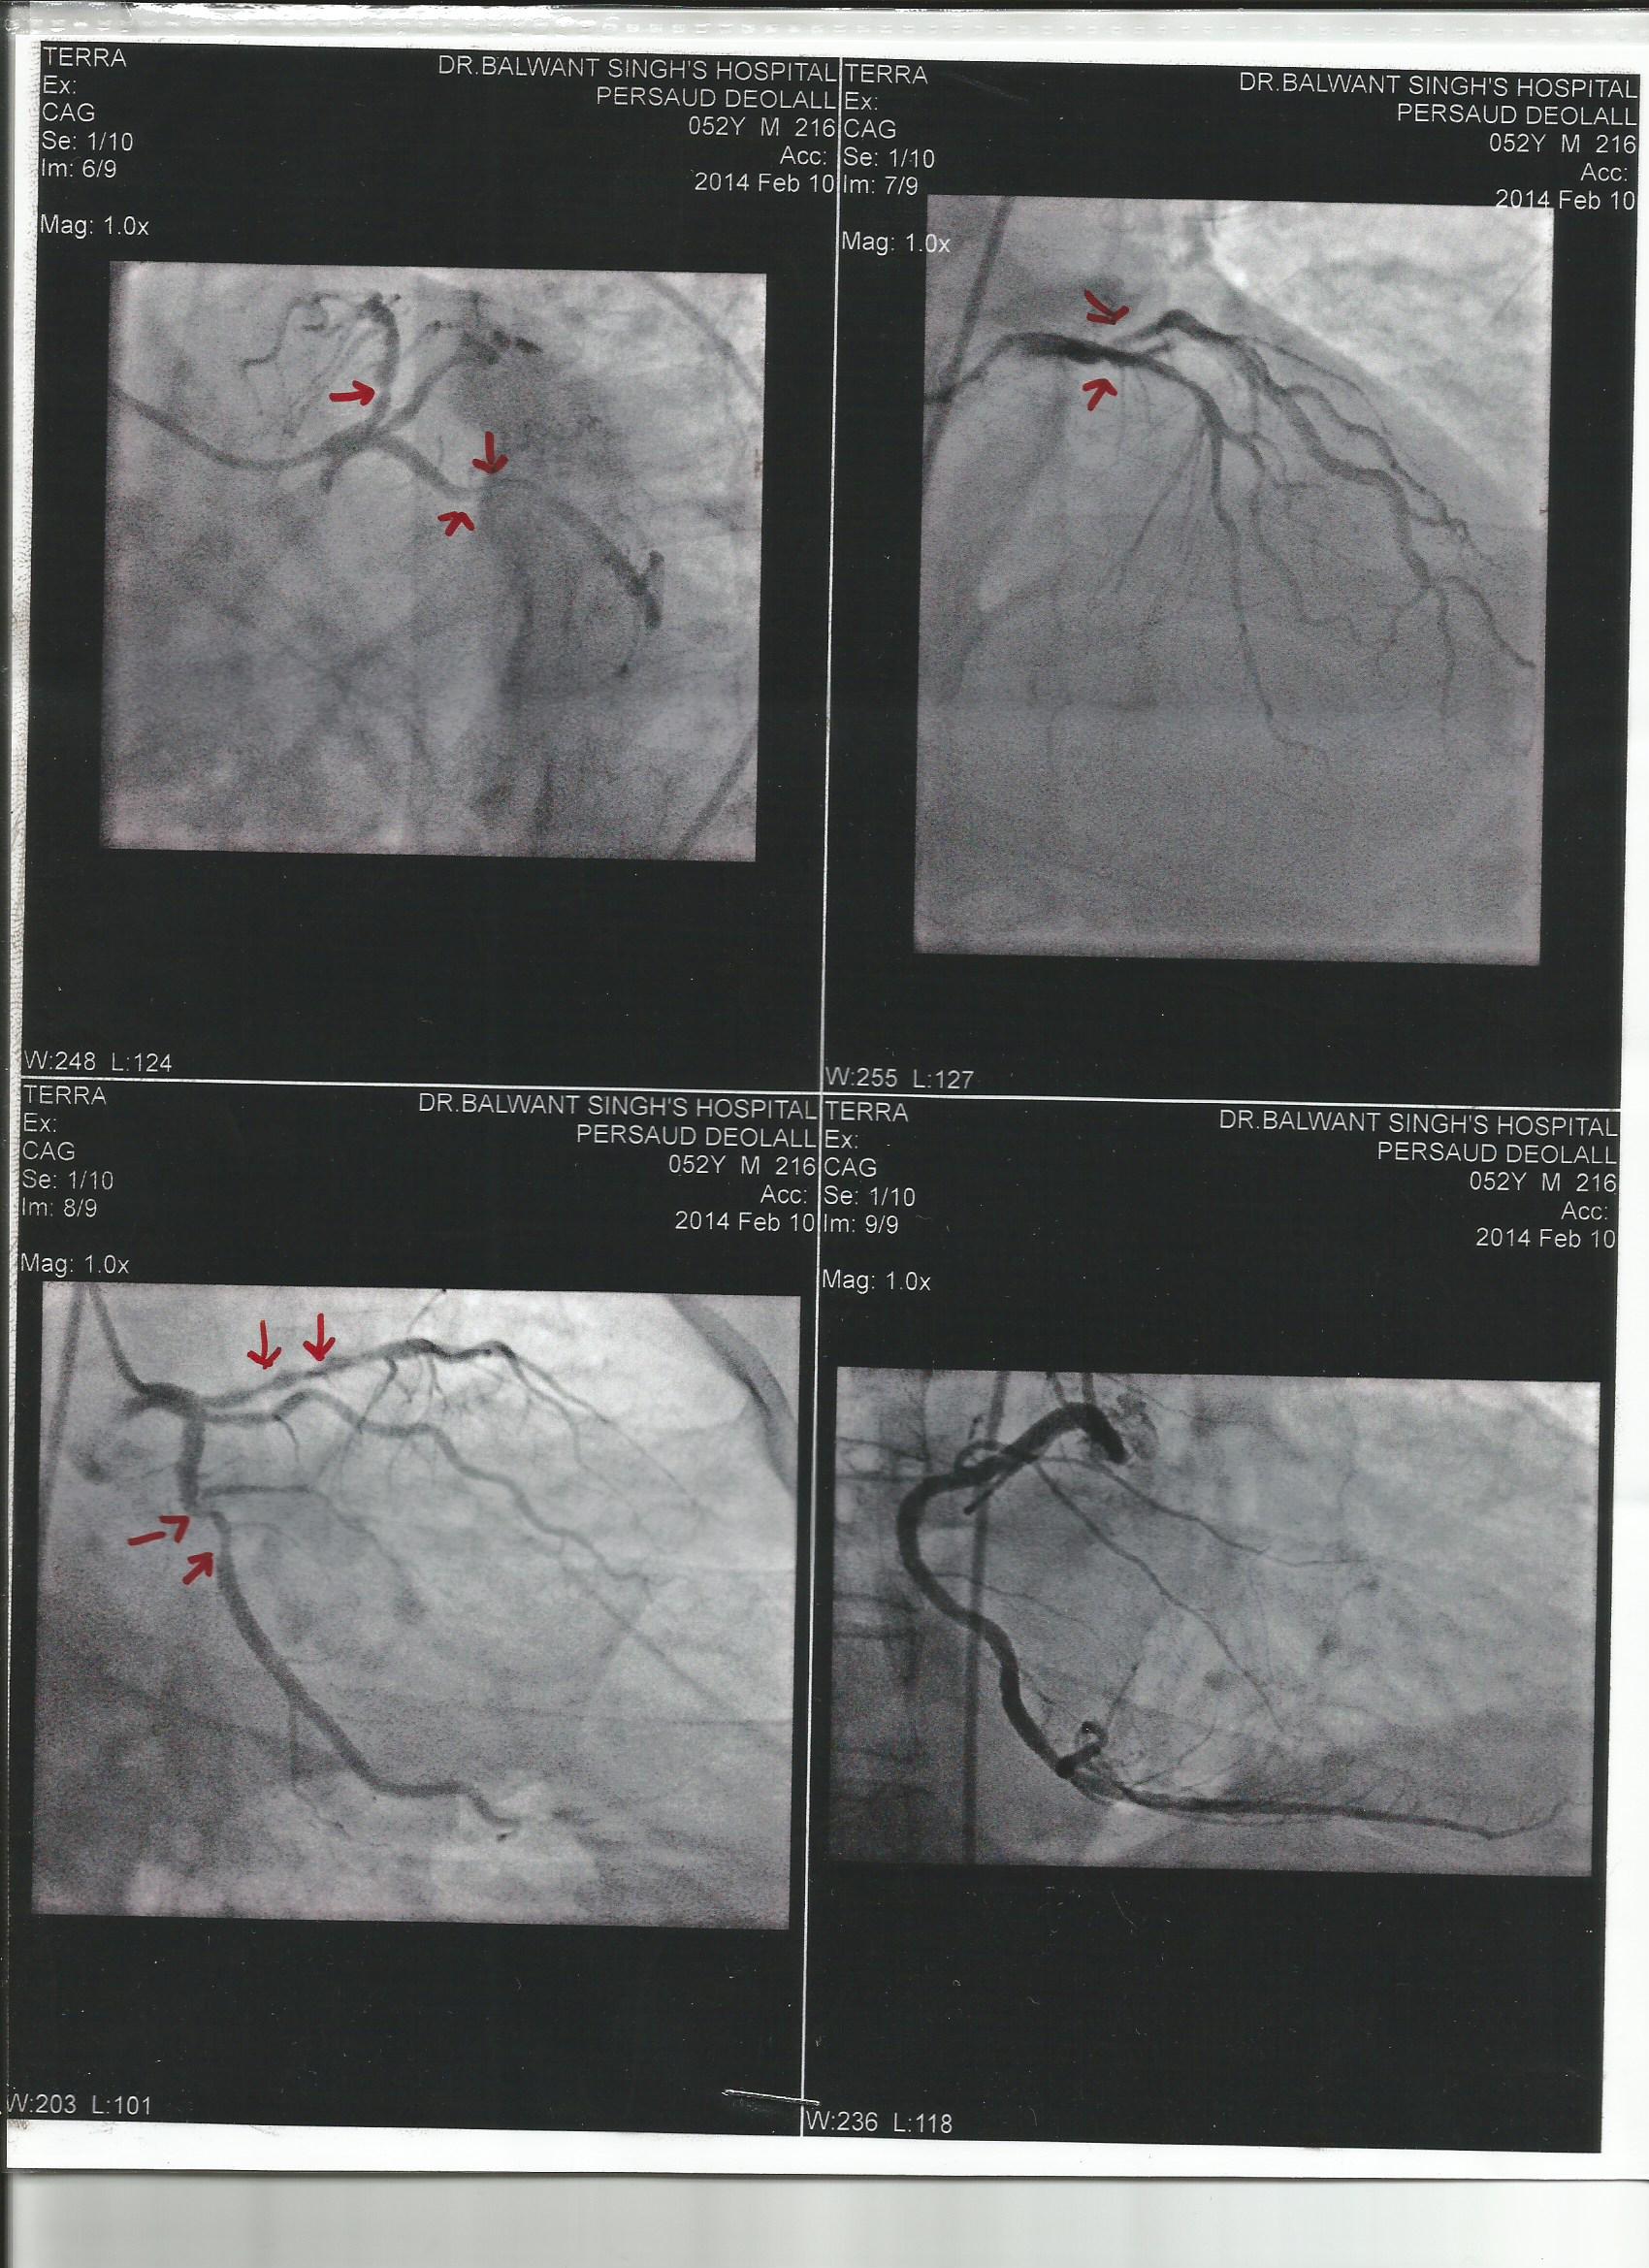

Our Brother Delolall Persaud has to undergo heart surgery and is asking for assistance. Please find attached an estimate from Balwant Singh’s Hospital for the cost of the surgery. Also attached is a scan showing the three blockages (red arrows)